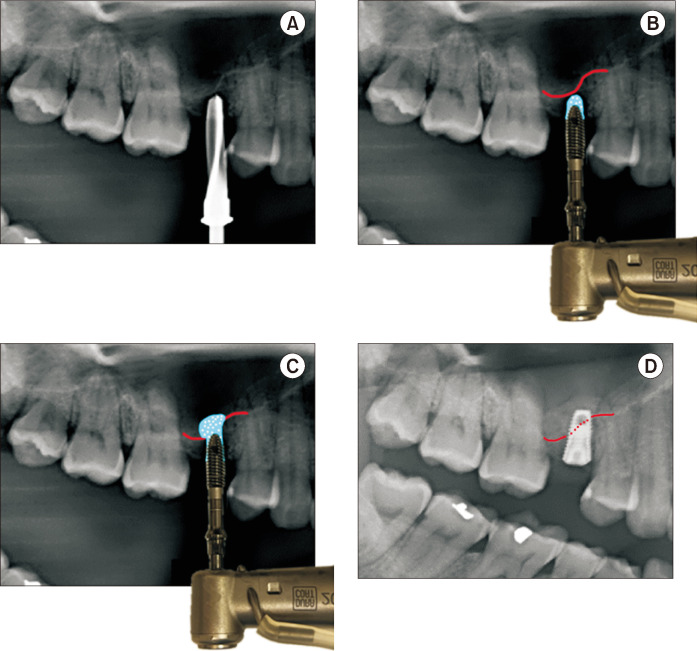

Transcrestal sinus floor elevation (tSFE) is a useful method for vertical bone augmentation in the posterior maxilla at the time of implant placement. However, this is a blind surgical technique with a risk of perforating the Schneiderian membrane. In this article, we present a simple technique to perform tSFEs using ridge spreaders. With this technique, the tSFE is performed in a slow and controlled manner without the entry of instruments into the maxillary sinus. Furthermore, many clinicians may find they already have the necessary surgical tools within their armamentarium. This precludes the need for rotary drills that spin at high revolutions per minute in the sinus cavity or osteotomes which may result in an uncomfortable patient experience. In order to fully exemplify its clinical utility in performing successful tSFE without membrane perforation, we present this surgical technique in a case with limited residual bone height and a steeply oblique sinus floor.